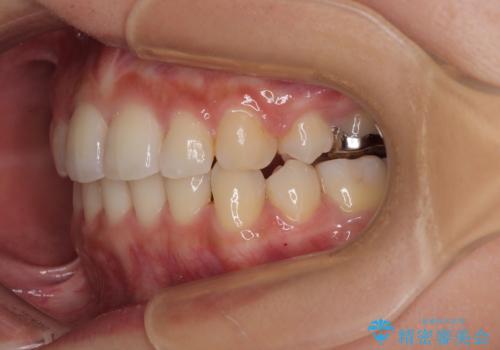

- 前歯のクロスバイトと口元の膨らんだ横顔の印象を気にして来院された患者様です。

しかしながら。そのまま叢生を解消すると横顔が突出した印象になる可能性が高かったため、上下左右の小臼歯4本を抜歯して、ワイヤー装置にて矯正治療を行うこととしました。

上下左右の第一小臼歯4本を抜歯して治療を行うことがセオリーでしたが、左下は第二小臼歯が銀歯であったため、イレギュラーではありますが、そちらを抜歯しました。

その影響で治療期間は長くなりましたが、処置していない歯を保存することができました。